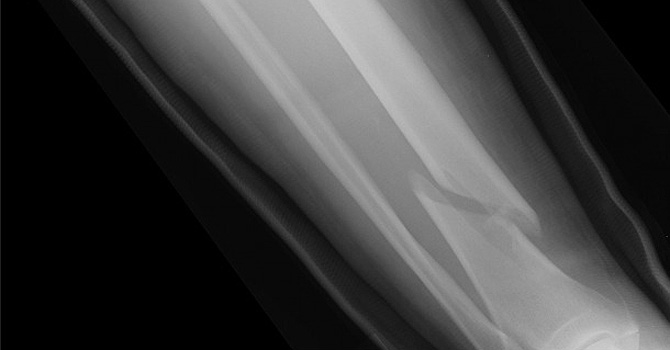

ٹوٹی ہڈیاں جوڑنے کی دوا تیار

broken leg-670

۔ — فائل فوٹو

طبی ماہرین نے دعوی کیا ہے کہ اب ٹوٹی ہوئی ہڈیوں کے مریض صرف ایک انجیکشن سے صحت یاب ہو سکیں گے۔

ڈان نیوز کے مطابق، ماہرین نے کئی برسوں کی تحقیق کے بعد ایک ایسی دوا تیار کر لی ہے جو ٹوٹی ہوئی ہڈیوں کو منٹوں میں جوڑ دے گی۔

یہ منفرد دوا پولی لیکٹک ایسڈ اور سرامک کے آمیزے سے تیار کی گئی ہے اور اسے مخصوص انجکشن کے ذریعے ہڈیوں میں داخل کرنے سے ان میں موجود دراڑیں فوری بھر جائیں گی ۔

طبی ماہرین کا کہنا ہے کہ نئی ایجاد سے نہ صرف ٹوٹی ہوئی ہڈیوں کو جوڑنے کے لیے تکلیف دہ آپریشن سے نجات مل جائے گی بلکہ آپریشن کے بعد کی پیچیدگیوں سے بھی چھٹکارا مل جائے گا۔